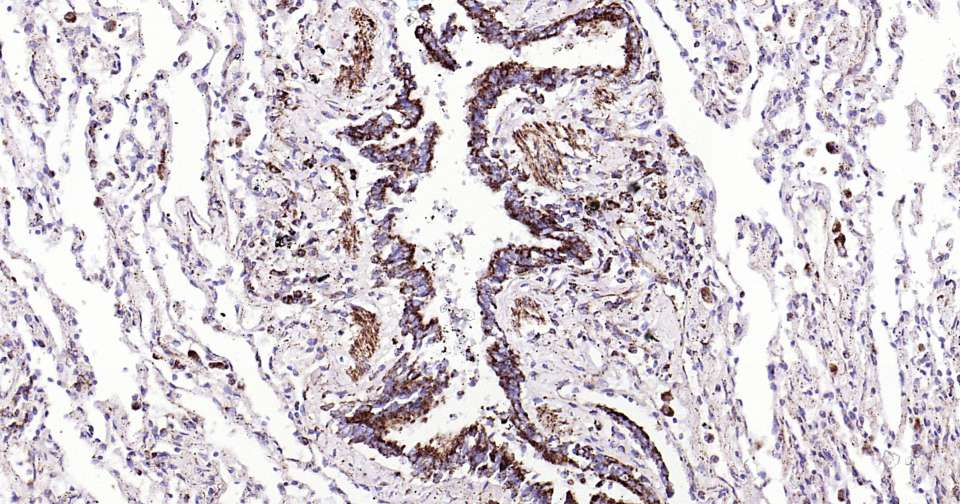

Immunohistochemical analysis of paraffin embedded human breast cancer tissue slide using IHC0317H (Human HSP60 Kit).

Immunohistochemical analysis of paraffin embedded human ovarian cancer tissue slide using IHC0317H (Human HSP60 Kit).

Immunohistochemical analysis of paraffin embedded human cervical cancer tissue slide using IHC0317H (Human HSP60 Kit).

Immunohistochemical analysis of paraffin embedded human liver tissue slide using IHC0317H (Human HSP60 Kit).

Immunohistochemical analysis of paraffin embedded human lung cancer tissue slide using IHC0317H (Human HSP60 Kit).

Immunohistochemical analysis of paraffin embedded human lung tissue slide using IHC0317H (Human HSP60 Kit).